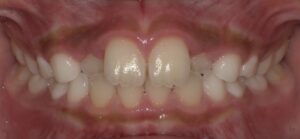

正面の写真ですが、真ん中から2番目の歯が

内側に移動し反対の噛み合わせになっています。